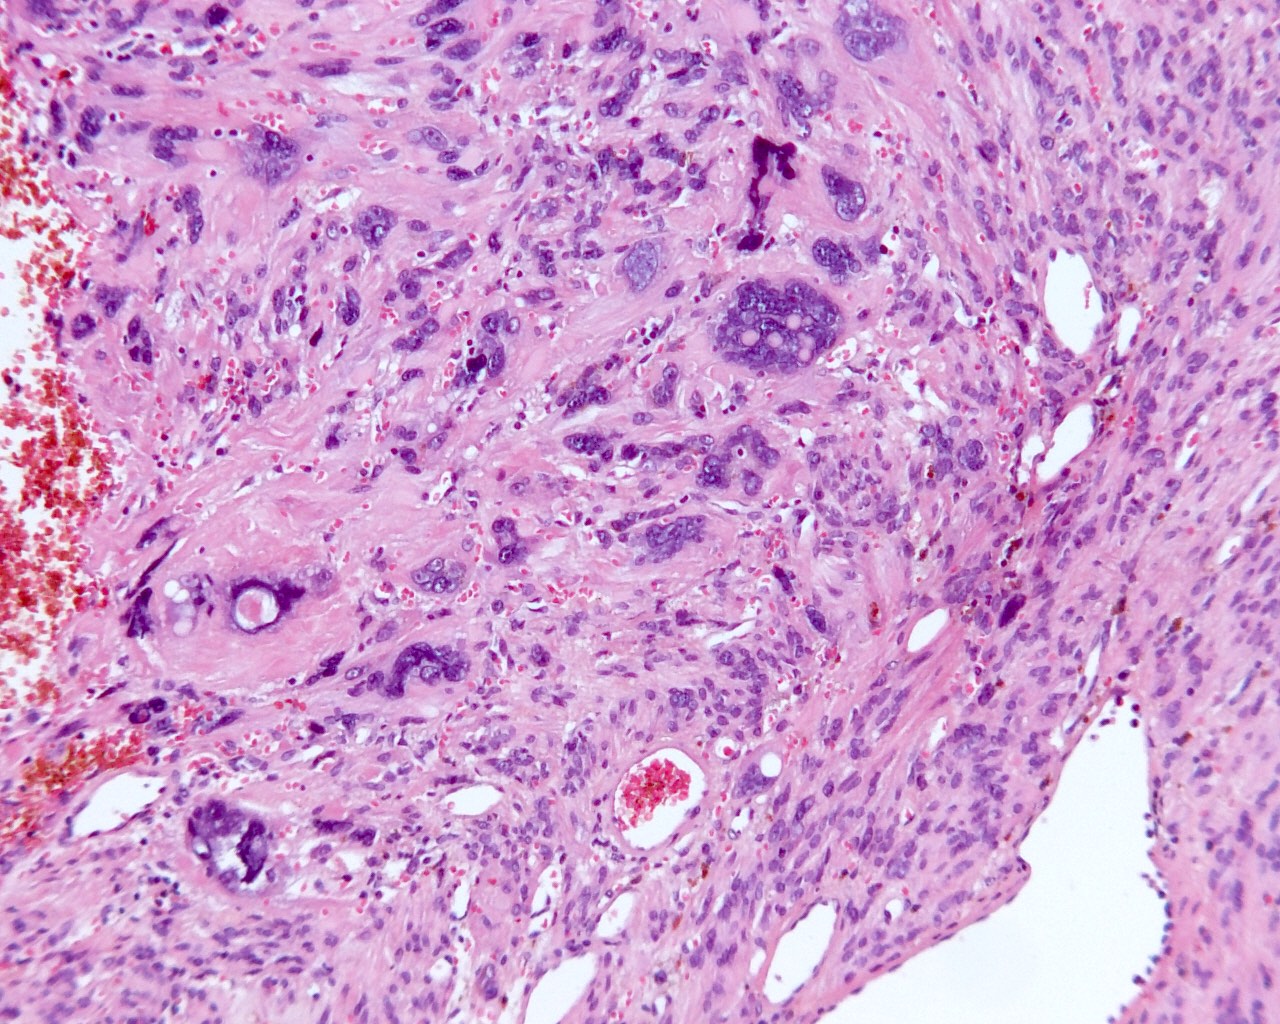

Microscopic (histologic) description

- Conventional / usual leiomyoma (spindle):

- Well defined borders

- Normocellular

- Intersecting fascicles of monotonous spindle cells with indistinct borders, eosinophilic cytoplasm, cigar shaped nuclei (with tapered ends) and small nucleoli

- Atypia: absent or mild

- Mitoses: rare (in general < 5/10 high power fields)

- Blood vessels with thick walls

- With or without infarct type necrosis, hyalinization, calcification, cystic change

- Leiomyoma with bizarre nuclei:

- Bizarrely shaped, hyperchromatic, multilobulated nuclei with nuclear pseudoinclusions

- Arranged in a multifocal to diffuse distribution in a background of a typical leiomyoma (Am J Surg Pathol 2014;38:1330, Mod Pathol 2017;30:1476, Am J Surg Pathol 2016;40:923, Cancer 2014;120:3165, Am J Surg Pathol 1997;21:1261)

- Alveolar edema, staghorn vessels

- Low mitotic activity (< 5 mitoses/10 high power fields)

- Absence of tumor cell necrosis

- Vasculature variable (staghorn vessels, thick walled vessels, fibrinoid necrosis of vessel walls, luminal vascular obliteration)

- Diagnostic key: intermixed normal spindled smooth muscle cells

Microscopic (histologic) images

Contributed by Sabrina Croce, M.D., Ph.D., Kristina Doytcheva, M.D., Jennifer A. Bennett, M.D. (Case #508) and @Andrew_Fltv on Twitter